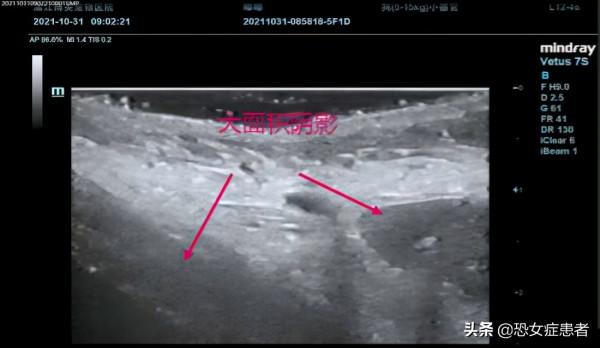

透過B 超可看到皮下有大面積液性暗區,是大面積淤血造成的。